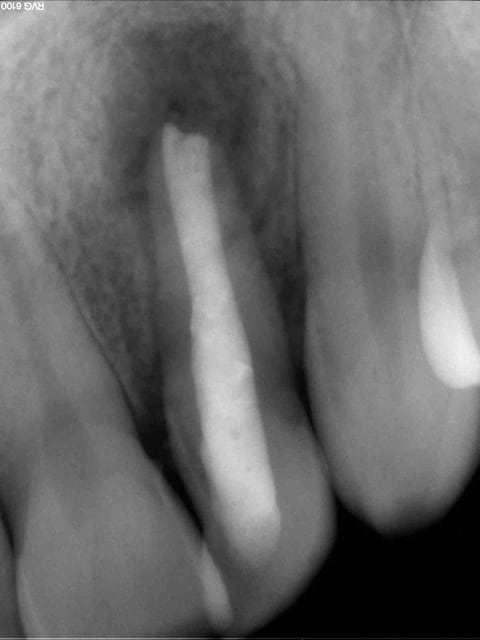

Patient, 20 ans, choc multiples sur les centrales étant gamin. Pano pour les 8.

Lésion sur 21, en bouche, légère dyschromie, test froid négatif, pas de douleur, retro, tu m'étonnes ... ! Les autres répondent correctement.

Concrètement, comment obturer convenablement ça ?

Bouchon de MTA : entre la galère pour appliquer ça correctement à l'apex et sans dépasser dans tous les sens, bof, de plus j'imagine que c'est utopique de vouloir obtenir ne serait-ce qu'un début de fermeture apicale.

Cônes de gutta moulés avec moultes Rx..., pourquoi pas, déjà fait, mais l'étanchéité ne semblerait pas optimale, ajouté au fait que le peu de ciment risque de fuser également.